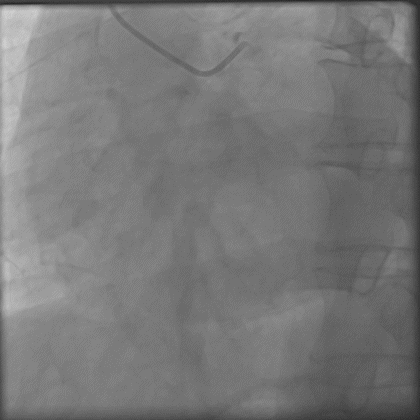

最终结果满意。